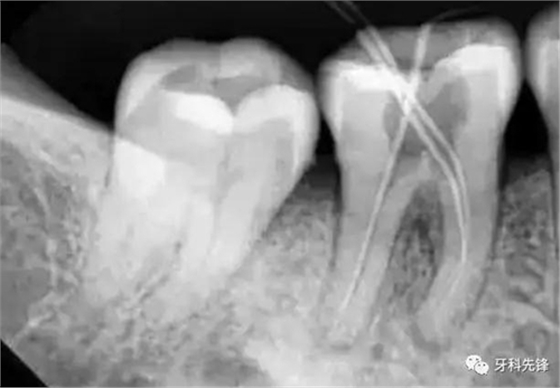

3、確定根管工作長度

應(yīng)用平行投照X線方法、根管長度測量儀確定根管度,最好插針拍X片。